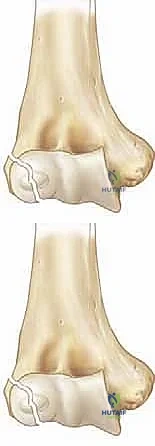

A profound, three-dimensional understanding of the distal humerus and its enveloping soft tissue envelope is paramount for successful surgical intervention. The lateral condyle is a complex, multi-tissue structure comprising the capitellum (the primary hemispherical articulation with the radial head) and a significant portion of the lateral metaphysis. Proximally, these fracture lines almost invariably originate in the posterolateral metaphysis. The fracture then propagates distally along the physis (the growth plate) before taking an abrupt turn to exit through the epiphysis.

The precise location where the fracture line exits the epiphysis forms the basis of the classic Milch classification, which has profound biomechanical implications. In a Milch Type I fracture, the line traverses the metaphysis and physis, then extends directly across the ossific nucleus of the capitellum. This is functionally analogous to a Salter-Harris type IV fracture. While less common, it strictly involves the lateral aspect of the joint. In contrast, the much more common Milch Type II fracture extends from the metaphysis, travels along the physis, and exits medially through the unossified trochlear groove, medial to the capitellar ossification center.

The Milch Type II pattern is inherently and significantly more unstable. By exiting through the apex of the trochlea, the fracture effectively destabilizes the lateral trochlear ridge. This ridge is the primary osseous buttress preventing lateral translation of the radioulnar complex. When this buttress is compromised, the entire forearm is permitted to subluxate laterally, carrying the fractured condylar fragment with it. Radiographically, a Milch Type II may deceptively resemble a Salter-Harris type II injury, but its intra-articular extension makes it functionally akin to a Salter-Harris type III or IV, demanding meticulous anatomical reduction.

Clinical & Radiographic Imaging Archive